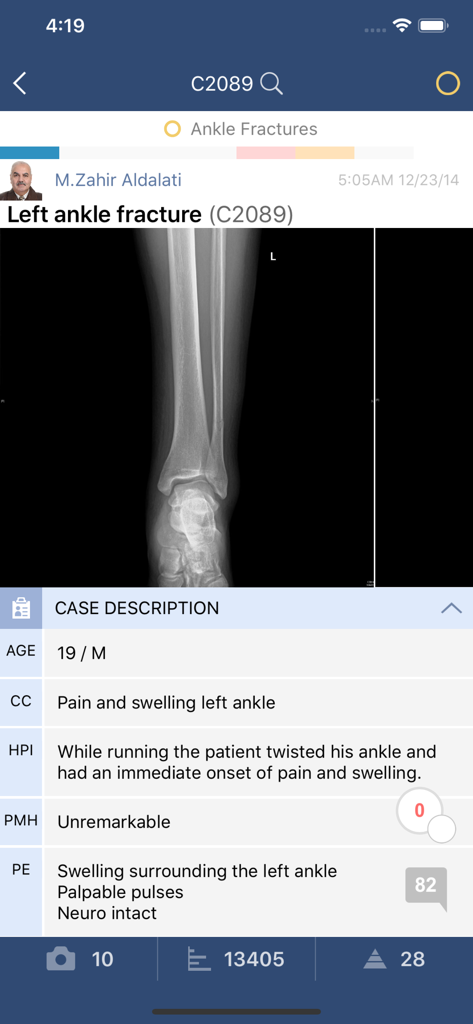

Bullets* - Clinical case study for a left ankle fracture in the Bullets app featuring an X-ray image and patient medical history

Clinical case study for a left ankle fracture in the Bullets app featuring an X-ray image and patient medical history